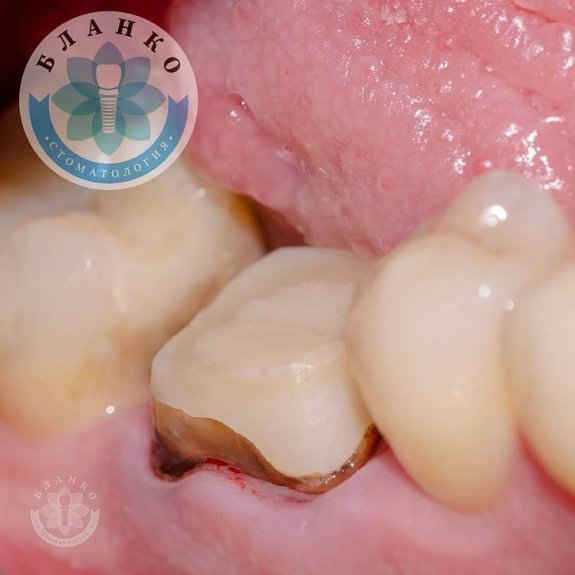

✳️На початковому знімку ми бачимо зуб 4.6 (обведений червоним кольором),в якому спостерігається хронічне запалення навколо коріння зуба та погана реставрація з пломбувального матеріалу, яка давно відійшла від тканин зуба і під якою розвинувся вторинний карієс (знімок №2).

- прибрано неспроможну реставрацію

- вилучено анкерні штифти